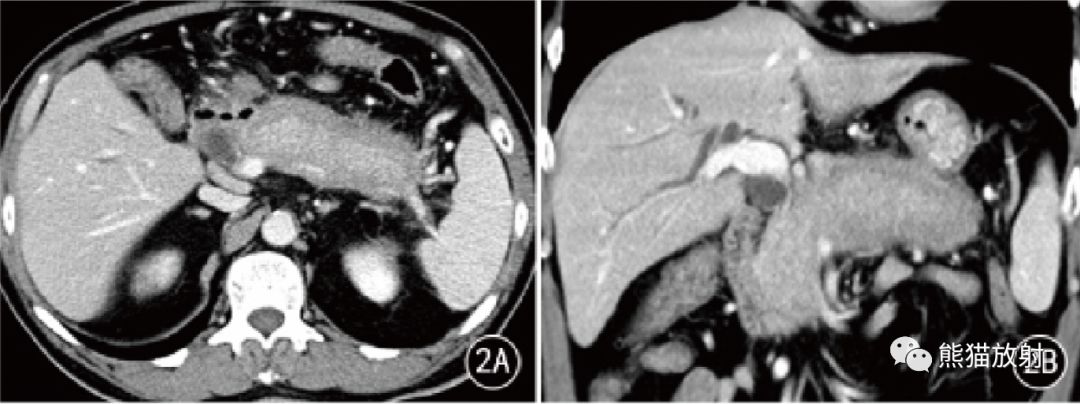

图 2 男,63岁。AIP 胰腺弥漫性病变, CT门静脉期胰腺弥漫性肿胀呈腊肠样,周围见包壳,胰管未见扩张,脾静脉变细狭窄;门静脉期冠状位重组胰腺段胆管狭窄,管壁增厚 。